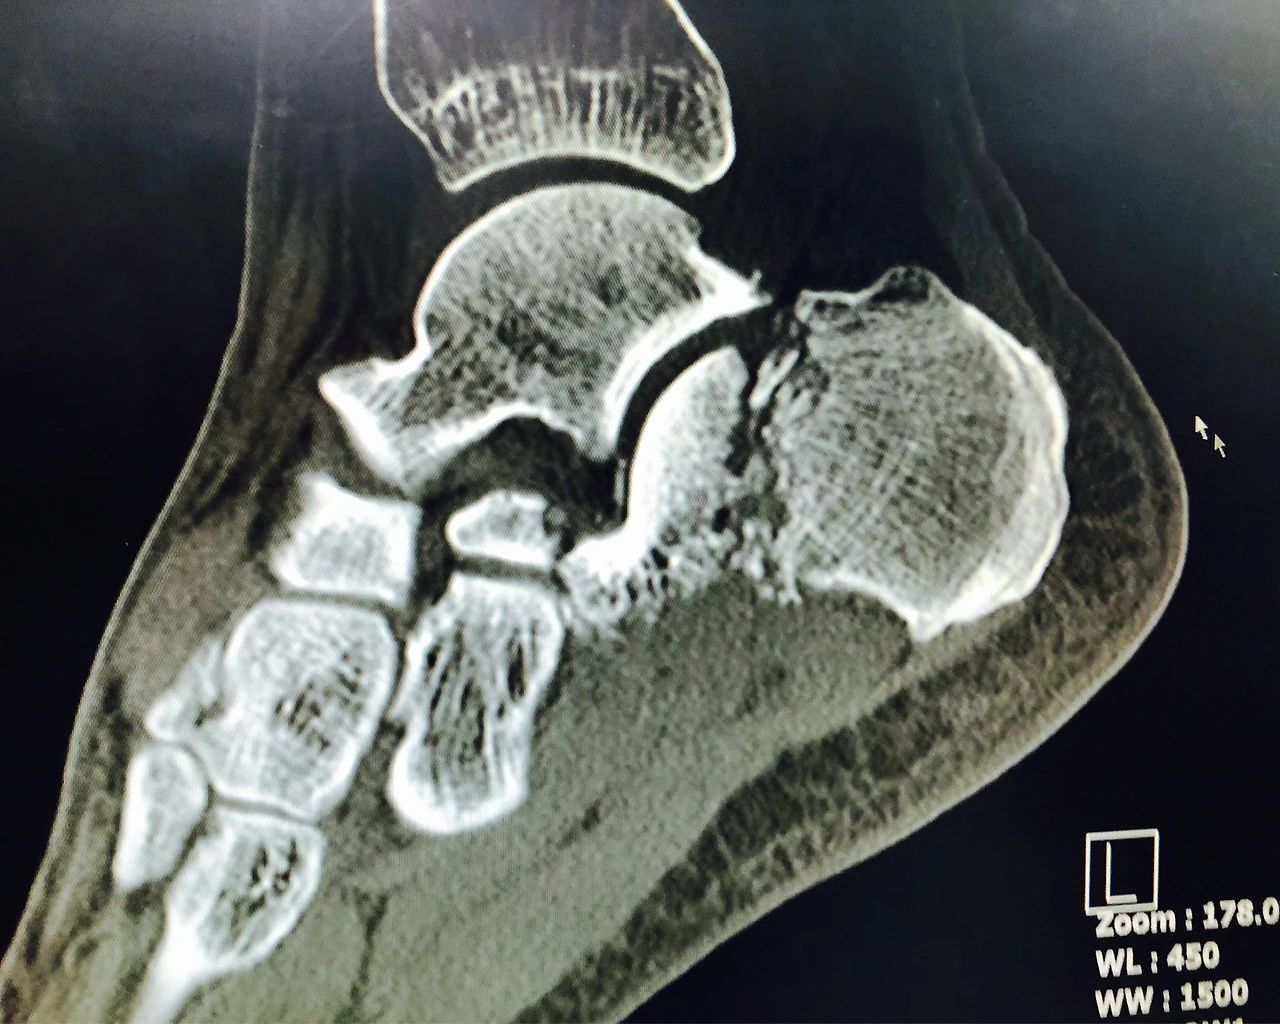

순간의 사고로 겪게 된 종골 골절! 내가 아프고 힘들어하는 모습을 굳이 글로 정리할 필요가 있을까? 난 병원에 누워 있으면서 - 남는 건 통증과 시간이었기에 - 관련 정보를 많이 찾아보며 종골 골절에 대한 다양한 경험을 간접적으로 느껴볼 수 있었다. 물론 그 내용들이 의학적으로 100% 맞는 얘기가 아닐 수 있지만 함께 경험을 이야기하는 것만으로도 사고의 아픔은 반으로 나누고, 회복의 기쁨은 배로 나누며 마음의 위로를 받기에는 충분했다.

종골 골절 병상일기는 추락사고로 인해 종골이 골절되어 입원, 수술, 회복, 재활과정을 직접 겪으며 적은 병상일기입니다. 의학적 판단보다는 개인적 경험을 위주로 하며, 그 경험을 나눌 수 있는 것만으로도 같은 환우들에게 도움을 줄 수 있기에 기록합니다. 궁금하신 점은 댓글로 남겨주시면 아는 만큼 답변드리겠습니다.